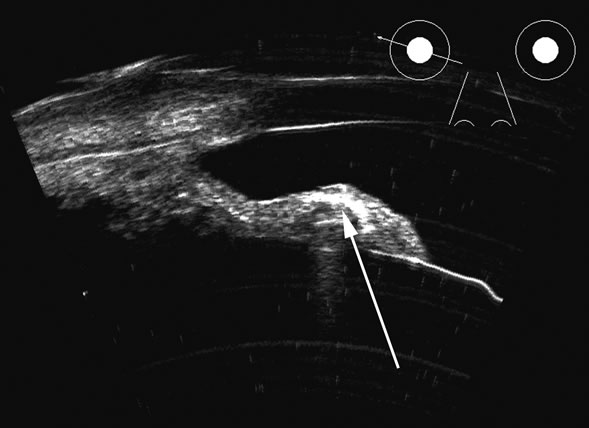

Vitreous foreign bodies are typically metal or glass objects, or intraocular

lens implants. The ultrasound examination, with its better spatial

resolution, is best performed following radiographic or computed tomography

examinations in order to identify the location and number of

foreign bodies. Ultrasonography is used to relate the position of a foreign

body to the retina and lens and identify coexisting structural changes, such

as retinal detachment. Metal and glass “absorb” or, more

correctly, deflect sound, so that an anechoic area appears

posterior to the foreign body. This area can act as an acoustic “pointer” to

the foreign body (Fig. 18). A-scan or gray scale on B-scan shows a highly reflective

surface of the foreign body. BBs and shotgun pellets often create

a “ringing” artifact that can also act as a pointer leading

to the foreign body.19 The foreign body can be easily demonstrated by lowering the gain; the

foreign body remains, whereas other, less reflective tissue planes fade

away due to a lower difference in acoustic impedance between tissues

than metallic or glass foreign bodies. Most foreign materials have a

higher density than the vitreous, and sound that passes through the foreign

body may appear to move the succeeding surface forward because of

the faster sound transit.